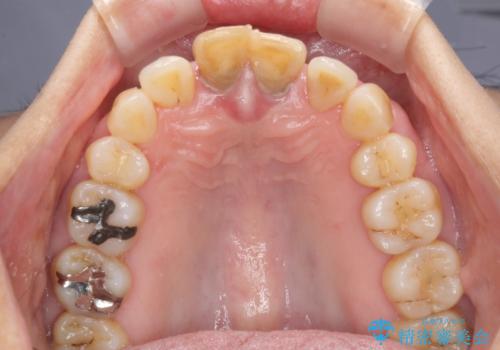

当初は上顎の補綴治療のみを希望されていましたが、奥歯にブリッジなど補綴物が多くあり、前歯も変色しているため、治療費が高額となってしまうことが懸念されました。

相談の上、最も気になっている前歯の部分矯正と補綴治療により口元の改善を図ることとしました。